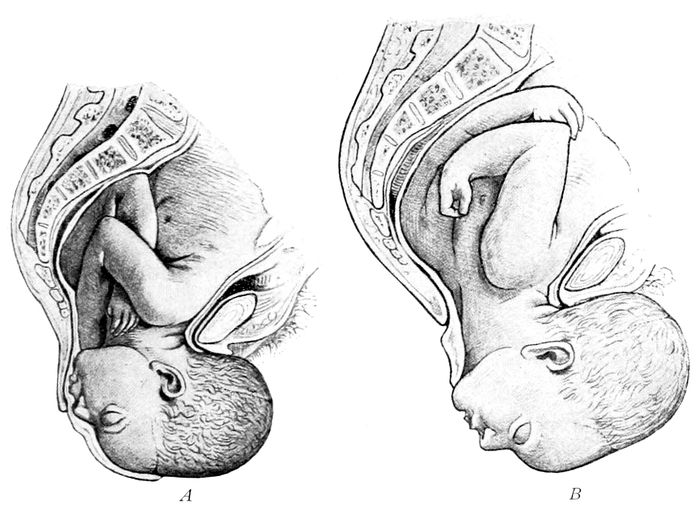

Extraction of the breech |

| |

Breech delivery. Extraction of the trunk |

| |